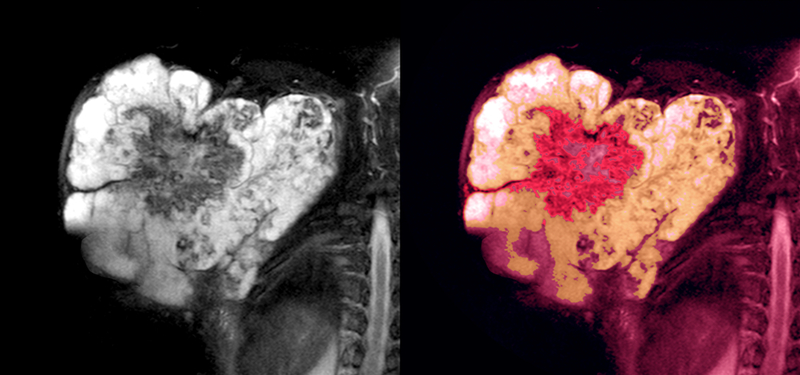

Doctors at Narayana Superspeciality Hospital, Howrah have performed the first Extracorporeal Radiotherapy (ECRT) case in Eastern India, where the cancer affected bone was taken out of the body for high intensity radiotherapy and then re-implanted post treatment.

In the second case, a 49-year old man came to Narayana Superspeciality Hospital Howrah when was unable to walk or sit due to excruciating pain around his pelvis for last seven months. After initial examination, radiological investigations and biopsy, he was diagnosed as a patient of chondrosarcoma of right pelvis bone. PET CT Scan revealed no evidence of disease anywhere in the body, so, he was treated with curative intent.

Dr Koushik Nandy, Ortho-Oncologist, Narayana Superspeciality Hospital Howrah, said, “The main challenge for this surgery was to give the patient a functional ambulatory life after the surgery. Operations in the pelvis involve extensive morbidity and post surgery functional deficit. In the multidisciplinary sarcoma board meeting, it was decided to plan for extracorporeal radiotherapy of the pelvis bone and re-implantation of the pelvis bone.” Mr Bhattacharrya recounted, “It’s been about six months that I got operated. Today I am free of the immense pain and can also walk with support.”